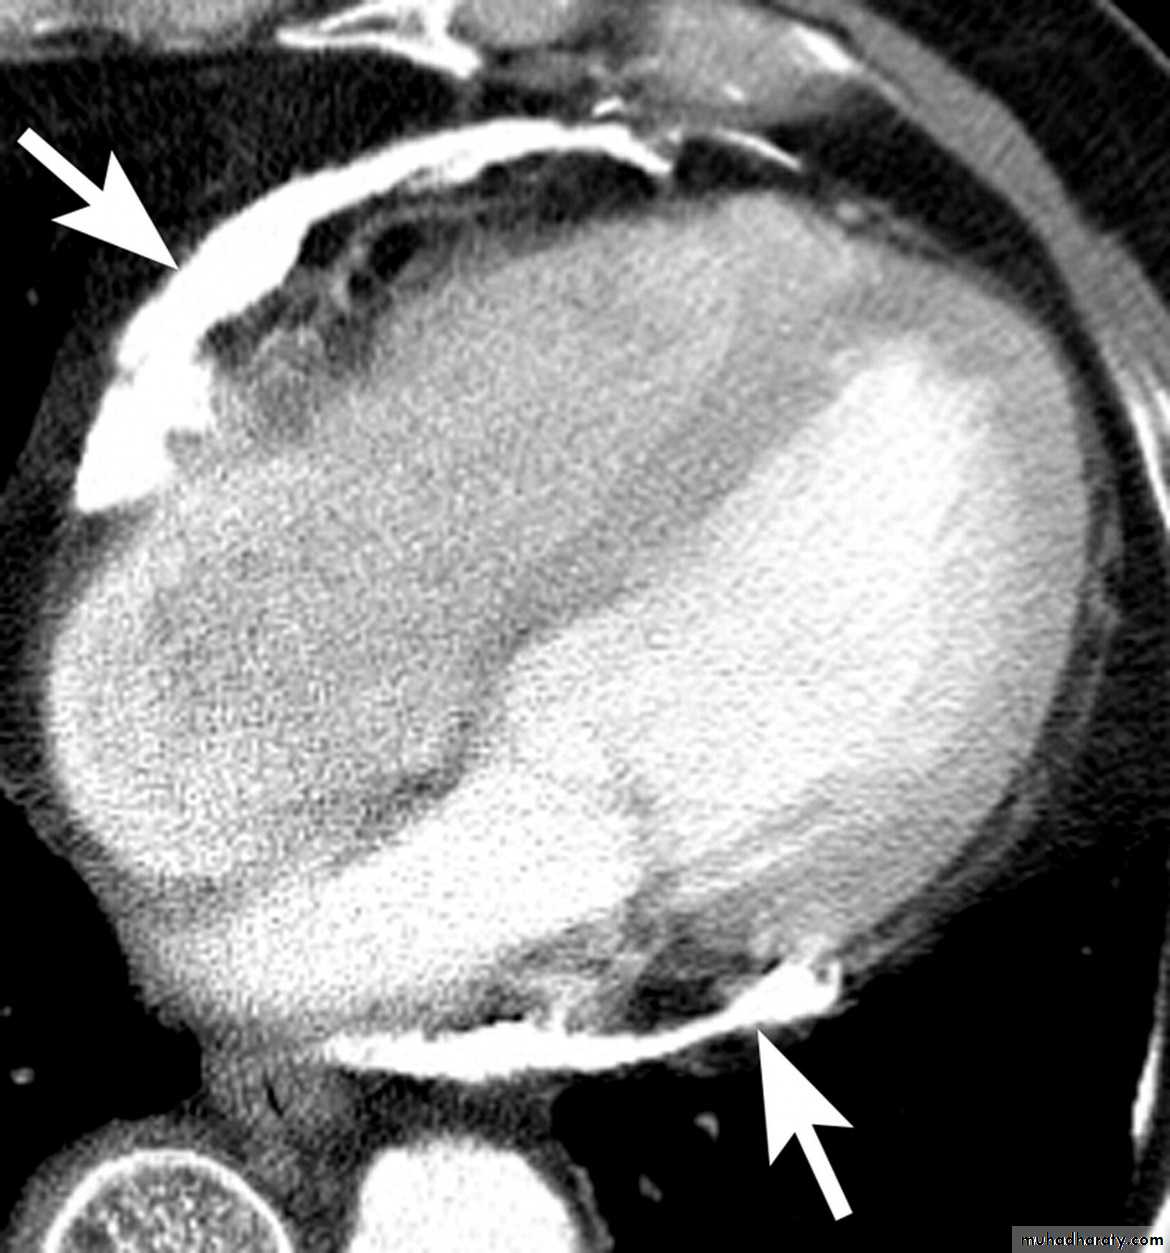

Acute Pericarditis: Investigation

CT scan & MRI:Demonstrate effusions

Define the pericardial & epicardial tissue

Investigations

Echocardiography & Doppler:RA & LA enlargement

Normal size ventricles

Pericardial thickening

CT/MRI: demonstrate the thickened pericardium